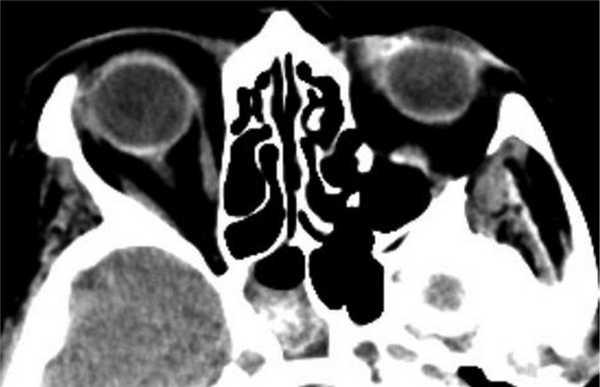

(Слева) На рисунке в корональной плоскости показаны классические признаки аллергического грибкового синусита (АГС), включая снижение пневматизации и вздутие нескольких придаточных пазух и полости носа. В центре виден плотный материал, окруженный по периферии отечной слизистой оболочкой.

(Справа) При аксиальной КТ без КУ определяется односторонний аллергический грибковый синусит. Пораженные пазухи вздуты и содержат плотный «выветренный» материал в центре, окруженный гиподенсным ободком по периферии. Поражение пазух при АГС может быть одно- или двухсторонним.

(Слева) На рисунке в корональной плоскости показаны классические признаки аллергического грибкового синусита (АГС), в т.ч. нарушение пневматизации и вздутие нескольких околоносовых пазух и полости носа. Уплотненный материал в центре окружен отечной слизистой оболочкой на периферии.

(Справа) На аксиальной КТ без КУ определяется односторонний АГС. Пораженные пазухи вздуты, сдержат уплотненный материал в центре, окруженный гиподенсным периферическим «ободком». Поражение пазух при АГС может быть одно- или двухсторонним.